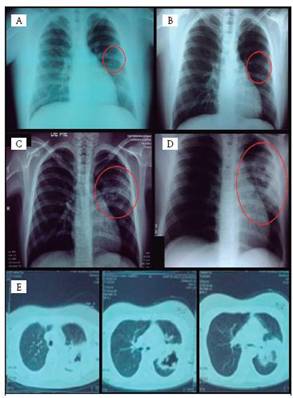

La radiografía de tórax inicial fue valorada como normal en este primer ingreso. Sin embargo, en la valoración retrospectiva en ingresos posteriores, se observó una imagen radiolúcida inespecífica a nivel del 5-6 espacio intercostal del pulmón izquierdo, con forma irregular y bordes lisos bien definidos (Figura 1, A-B).

El niño se ausentó a la cita control y reingresa 2 meses después con fiebre, pérdida de peso (13Kg) y empeoramiento de su debilidad muscular. Se encontró un paciente febril, desgastado, con lesiones de piel residuales, con dificultad para deambular y subir gradas, y con signo de Gowers positivo. Presentaba tos sin expectoración, con auscultación de sibilancias bilaterales y disminución simétrica del murmullo vesicular. Además, se describió hepatoesplenomegalia. Los estudios de laboratorio mostraron elevación de transaminasas, CPK y proteína C reactiva, hipoalbuminemia, leucocitosis con predominio de polimorfonucleares y trombocitosis (Cuadro 1). Un ultrasonido de abdomen mostró esteatosis hepática y esplenomegalia. Una radiografía de tórax mostró atrape aéreo y un infiltrado intersticial con tendencia a la consolidación en pulmón izquierdo a nivel de 4-6 espacio intercostal (Figura 1, C). Debido al cuadro clínico, la evolución y los datos reportados en las biopsias de músculo y piel, se inició tratamiento con metilprednisolona a 1g/día IV por tres días, para luego trasladar a prednisona VO. Sin embargo, el niño inició con hipertensión arterial sintomática (153/105 mmHg), lo que obligó a reducir los esteroides e iniciar enalapril. Cursó normotenso, con mejoría clínica, y disminuyeron la CPK, la leucocitosis y la PCR. Egresó afebril con mejoría de su problema muscular: podía deambular, realizar cuclillas y levantarse sin dificultad; sin lesiones en piel; con presión arterial normal. Se le indicó continuar el tratamiento con prednisona y enalapril y mantener el tratamiento para el asma y la epilepsia.

Dos meses después reingresó sin tratamiento durante el último mes y con pérdida de peso (4Kg), fiebre, tos con expectoración, debilidad muscular y mialgias, con gran limitación para efectuar las actividades de la rutina diaria. El examen físico mostró un niño muy desgastado y con dificultad para movilizarse por sí mismo. Presentaba artralgias en rodillas, fuerza muscular 3/5 en extremidades y reflejos osteotendinosos normales. A la auscultación pulmonar tenía sibilancias y disminución del murmullo vesicular izquierdo. La radiografía de tórax se reportó con atrape aéreo, una lesión cavitada en lóbulo superior izquierdo, con broncograma aéreo sin niveles hidroaéreos y leve borramiento de la silueta cardíaca (Figura 1, D). Un TAC de tórax confirmó una lesión de consolidación densa en el segmento posterior del lóbulo superior izquierdo con cavitación central, de contenido aéreo con comunicación con la vía aérea, con infiltrado nodular periférico y escaso líquido pleural ipsilateral (Figura 1, E). Se hizo una broncoscopía con lavado bronquialveolar y cepillado bronquial, lo que permitió el aislamiento de Mycobacterium tuberculosis. Además, presentó un síndrome de secreción inadecuada de hormona antidiúretica que se resolvió satisfactoriamente.